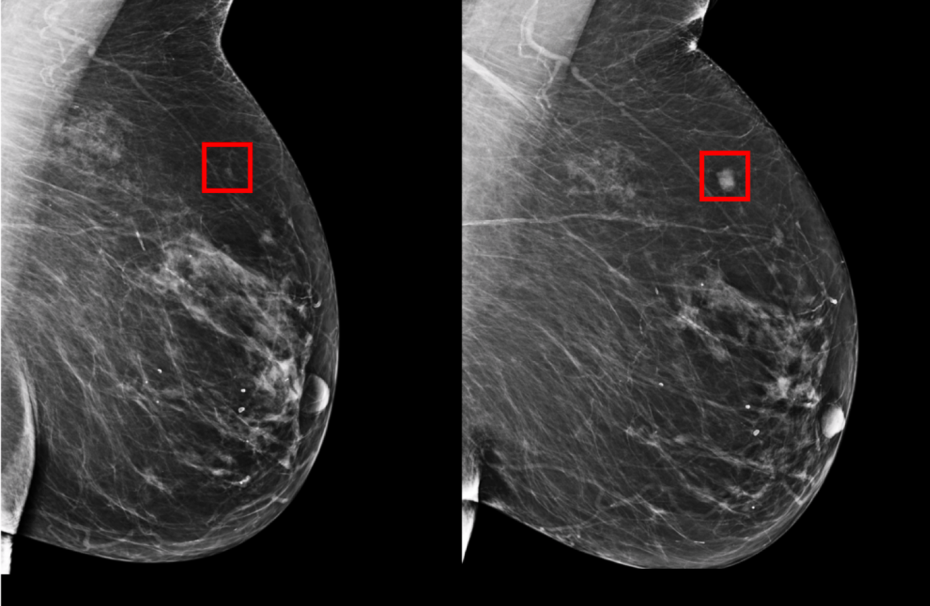

Сегодня с помощью технологий искусственного интеллекта (artificial intelligence, AI) американские ученые из Лаборатории информатики и искусственного интеллекта Массачусетского технологического института и Главной больницы штата Массачусетс разрабатывают решение для более последовательных и надежных процедур скрининга. В опубликованной статье в журнале Radiology они описывают модель машинного обучения, которая на основе данных маммографии может предсказать, может ли у пациента развиться рак молочной железы в будущем за пять лет до начала заболевания.

Ученые МТИ отказались от использования ручного метода диагностики и идентификации рисков в пользу системы, обученной на данных более чем 90 000 маммографий и известных результатов у более чем 60 000 пациентов Массачусетской больницы общего профиля. С помощью этих данных система "научилась распознавать" взаимосвязи между данными, которые могут упустить даже высококвалифицированные радиологи и онкологи.